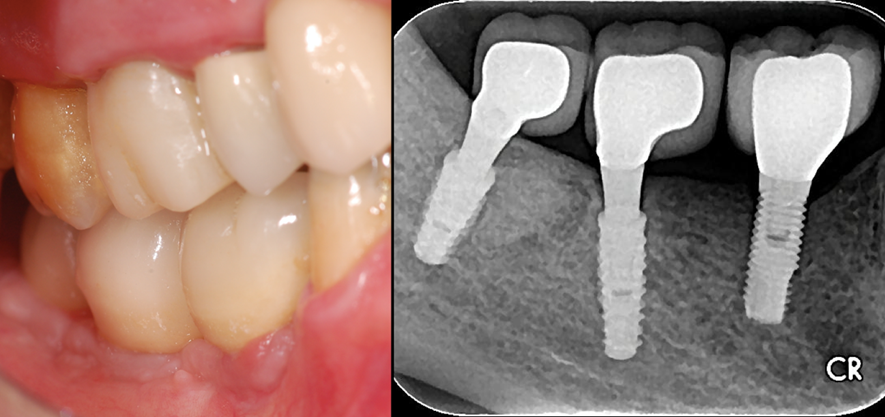

Figura 3 – Imagens clínica e radiográfica no momento da colocação das coroas sobre os implantes 46 e 47 – Cone Morse Maestro (Implacil Osstem – São Paulo – Brasil). Observar a normalidade do tecido ósseo peri-implantar.